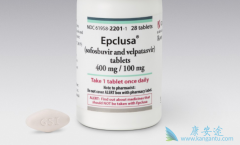

针对丙肝患研发出来的新药物已经经过世界卫生组织批准,预示着丙肝病毒已经被人类所攻克, 丙肝 是直接通过病毒的药物来获新成分因子。到现在为止目前最有效的丙肝新药 吉三代 的治愈率可达99%。但是目前来说丙肝能达到临床治愈的效果,只有仅有部分人群。 ...

基于 索磷布韦 的DAA方案是非常有效且得到广泛推荐的药物,但由于过去数据不足,严重肾损害人群在应用索磷布韦时会比较谨慎,但现在有更多的数据和经验提示了索磷布韦方案较好的疗效和安全性。 所有的DAA药物都是经过肝或者肾代谢的,大部分经过肝脏 ...

原则上, 来迪派韦索磷布韦 对于基因1型成人患者,它的证据最强,但事实上该药对其他基因型,即基因1、2、4~6型患者的治疗效果也很好。尤其是在东亚地区,基因2型是第二常见的HCV基因型,在这个人群,一些较大的亚洲的临床试验看起来效果也都不错。去年 ...

目前, 中国的丙肝患者已经可以使用进口的丙肝直接抗病毒药物治疗,这些药物中,大家比较熟悉的就是吉利德旗下的丙肝新药吉三代。早在吉三代还没有在国内上市之前,丙肝患者都会选择使用印度吉三代仿制药来治疗,吉三代由于良好的治疗效果,广泛的适应范 ...

丙肝目前首选的治疗药物是吉三代代表的口服直接抗病毒药物,直接口欧抗病毒药物的上市,丙肝的治疗变得非常简单。通过口服药物的治疗,丙肝可以试下治愈,这一点是与乙肝有着很大不同的。目前丙肝的治疗药物,主要是吉利德旗下的几代抗病毒药,无论是第 ...

丙肝的治疗 经历了干扰素时代后,从索非布韦开始进入到了直接抗病毒药物时代。口服直接抗病毒药物的出现,将丙肝从一个较难治愈的治病变成了一个通过口服药物就可以治愈的疾病。而在索非布韦之后上市的 吉三代 等药物,更是成为了丙肝患者的治疗首选。 ...

吉利德旗下的丙肝治疗药物从第一代索非布韦发展到了新一代 吉四代 Vosevi,药物的不断发展带来的是更短的治疗时间以及更广阔的适应症范围,目前吉利德旗下的丙肝治疗药物是丙肝患者的治疗首选。吉利德丙肝药“ Vosevi ”(商品名)在中国提交免临床上市 ...

今天(6月12日),国家药品监督管理局药品审评中心官网显示,吉利德的 丙肝新药 “索磷布韦/维帕他韦/伏西瑞韦片”(Vosevi)在中国的上市申请获得承办,受理号为JXHS1900078。Vosevi由三种固定剂量成分组成,分别为sofosbuvir(索磷布韦,400mg)、velp ...